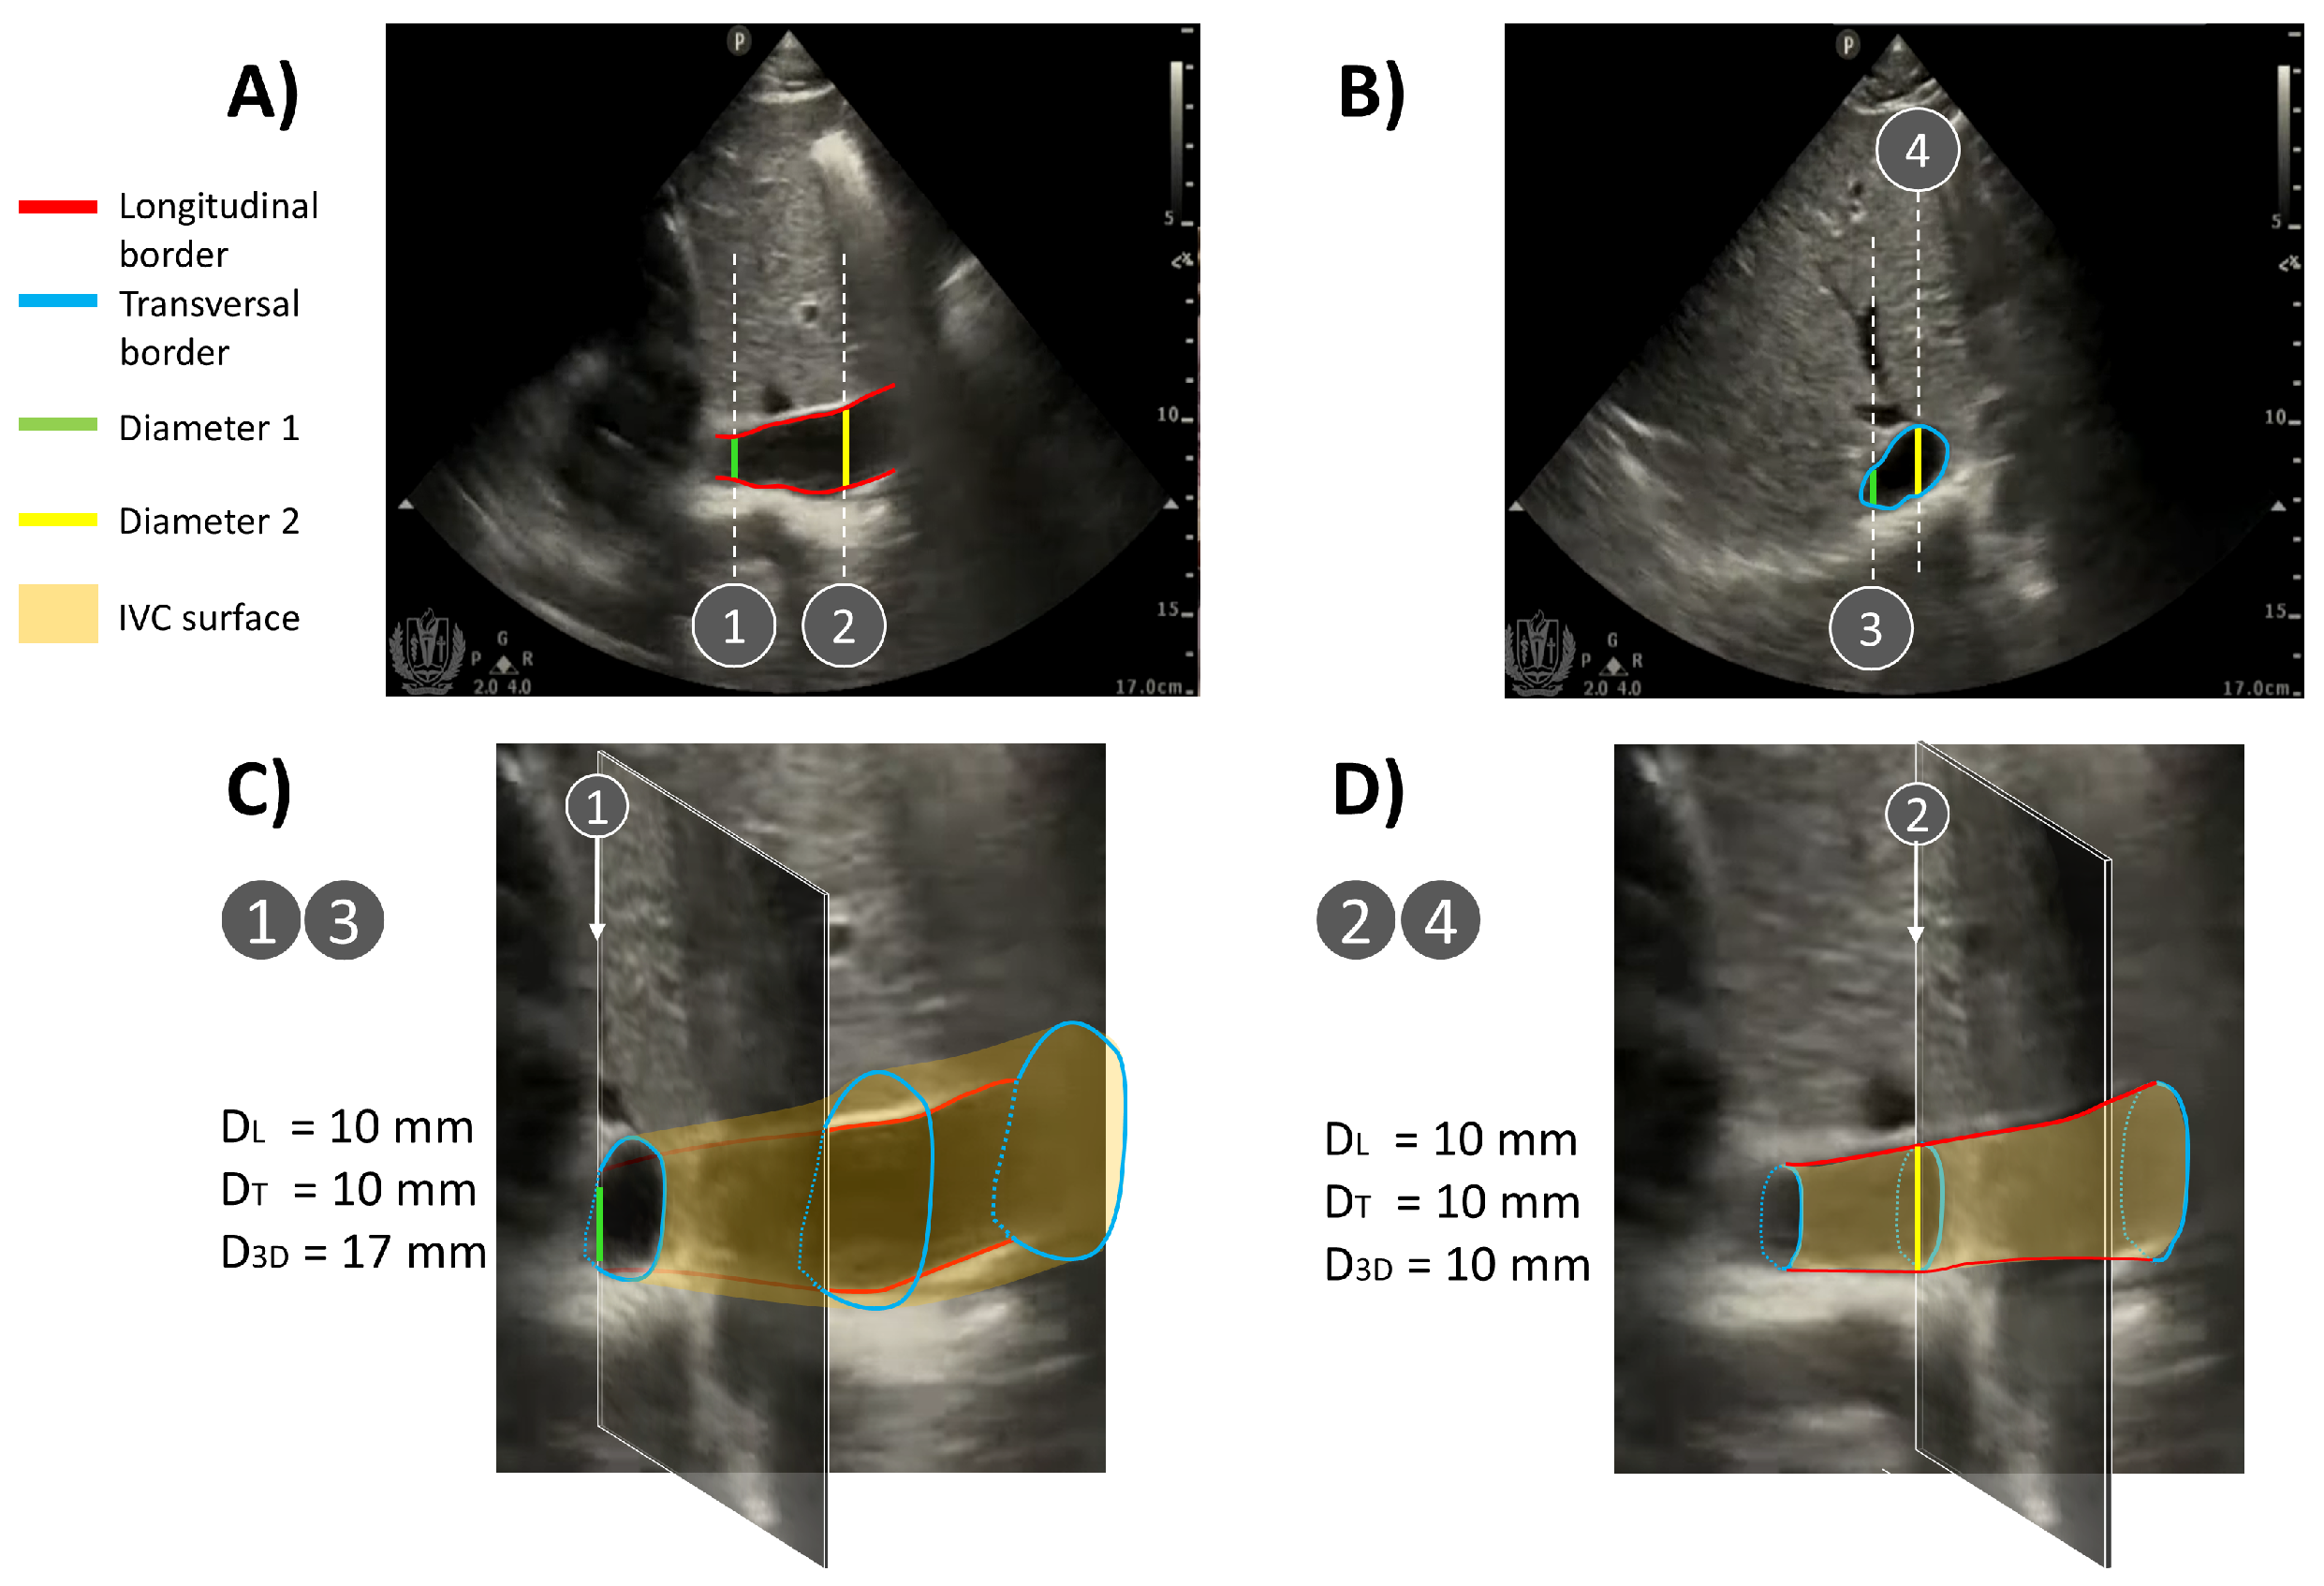

In practice, a combination of different movements of the IVC is expected in experimental recordings. They cannot be inspected in detail by two sequential acquisitions in B-mode in long and short axes (which could be aligned by synchronizing them with respect to the respiration and heart cycles). Indeed, the additional information of the relative position of the two scanning planes would not be available in that case, but it is fundamental. Figure 8 provides a sketched representation of this situation, considering a pair of frames of experimental data in B-mode. They show the IVC in long and short axes, respectively. As it is not possible to precisely control the relative locations of the scanned planes in B-mode, we assumed that the recorded frames resulted from two different sections, related by a longitudinal displacement of the cross-section (as in Figure 4) together with a medio-lateral shift of the longitudinal section (as in Figure 5) to obtain compatible configurations. Two very different IVC geometries are required to justify the two recorded frames in those conditions. Accordingly, different volumes and equivalent diameters would be needed to correctly characterize the vein, which are not available with neither single nor sequential B-mode acquisitions. Notice that Figure 8 shows only two examples of configurations, but the considered two frames could were taken from IVCs with other geometries: for example, the cross-section could have been acquired with a pitch angle with respect to the IVC axis (investigated in Figure 6), providing a bias in estimating the equivalent diameter, which would be larger than that of the true cross-section of the studied portion.

Figure 8. Representative example of two different IVC geometries compatible with the same two B-mode acquisitions in (A) long and (B) short axes, respectively (frames extracted from [26]). The two frames are assumed to be taken in the same conditions (i.e., ideally in the same time sample or at the same point along the respiratory and heartbeat cycles), but without knowing the direction of each scanning plane (available only in X-plane mode). Very different IVC geometries can be deduced, depending on the relative positions of the scanning planes, obtaining different estimations of equivalent diameters (DL, DT, and D3D, which are the estimated equivalent diameters from the longitudinal, transversal, and X-plane views, respectively). (C) If the long-axis plane is displaced in the medio-lateral direction with respect to the center of the IVC, the two frames are compatible with an IVC with a large volume (notice that the green segment has the same length in the frames shown in the top panel). (D) If the long-axis section is on the IVC axis, the volume of the vein is much smaller than in the previous case (notice that the yellow segment has the same length in the frames shown in the top panel).